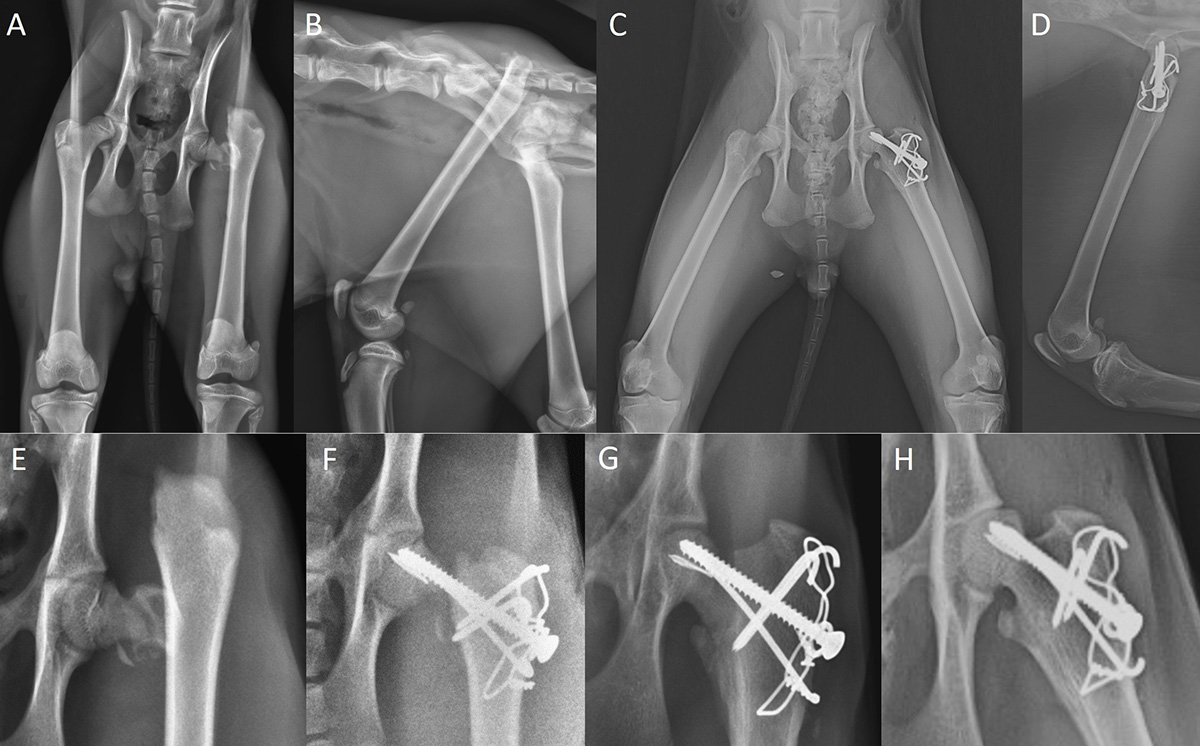

Presenting with a fractured femoral neck and additional avulsion fracture of the greater trochanter, the bobcat, if left untreated, likely would have had limited use of the limb due to nonfunctional malunion. Without treatment, the bobcat likely would have ended up in a zoo or similar facility; euthanasia was never an option. The rescue organization’s main goal is to recover injured wildlife and then release them—and all animals receive the same dedication and care, whether opossum, rat, or bobcat.

The treatment included placement of a screw with a washer and a pin to reestablish the femoral neck, and a tension band to secure the trochanter.

“His young age was the only reason this surgery was a success. During the procedure, I knew this was not going to look good on post-op radiographs. Indeed, when I saw those films, I was more or less convinced it would fall apart, especially knowing that this was a wild, energetic bobcat,” von Pfeil notes. “Only the dedicated care of Laura’s team—and the extremely good cooperation between us to stage the recovery process—allowed this injury to heal.”